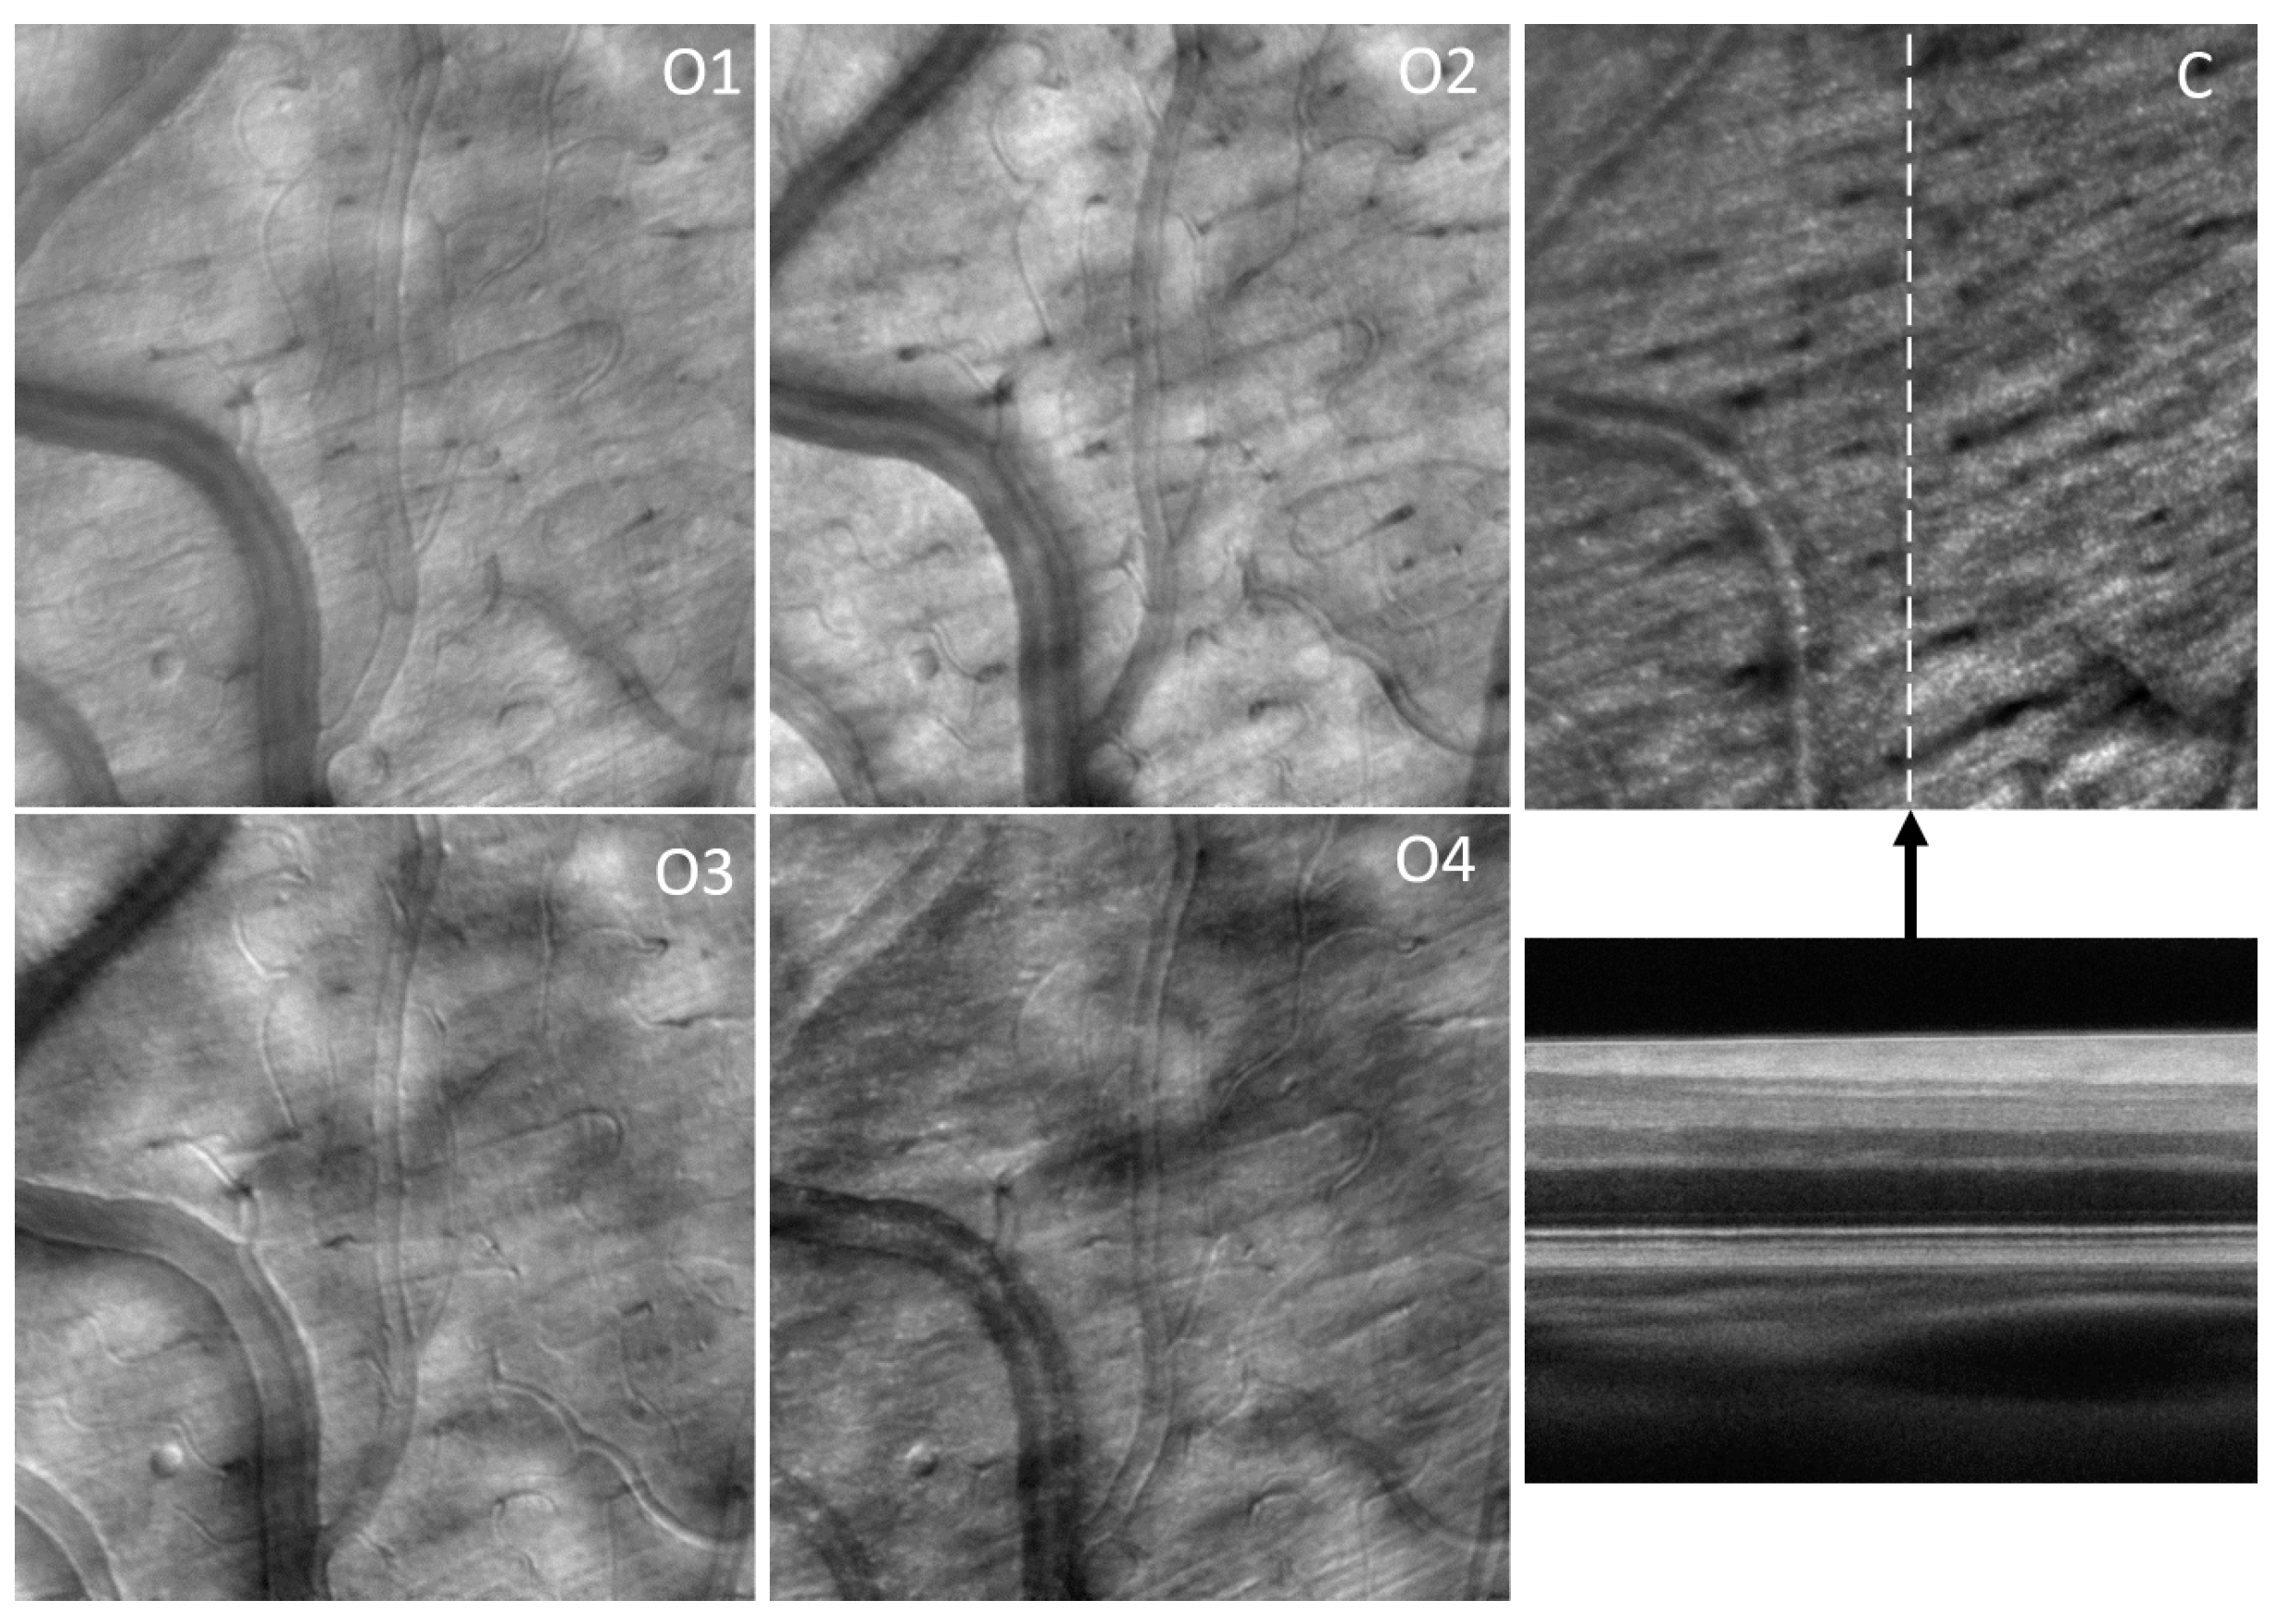

Figure 17 shows an example of the four offset images (O1–4) and the confocal (C) image simultaneously acquired with the OCT B-scan from a healthy subject. Figure 18 shows all the images derived from these four offsets: SPL 1–4, S, STD, SD, P, and PG. Figure 19 and Figure 20 show the images from glaucoma patients obtained at NYU with the upgraded CAORI (with flying-spot SLO and fiber bundle multi-offset detection).

A third version of CAORI has been converted to the flying-spot AO-SLO configuration, and the detection module consists of the fiber bundle simultaneously acquiring the confocal and the four offset channels, as in MAORI. Figure 17 shows an example of the acquired images (C and O 1–4), and Figure 18 shows the derived images (SPL 1–4, SD, PG, STD, and S). It should be noted here that SD, STD, S, and PG are all isotropic, direction-independent, as they were derived from all four offset images and are, therefore, directionally diverse. STD extraordinarily reveals the maps of capillaries with much better contrast than in any other imaging modality, in a mode similar to OCTA. STD can also be used to segment the flow location in large vessels and to quantify the inside diameter of the vessels. The complementarity of the derived images should also be noted in Figure 18. Some edges, like the vessel wall and some capillaries, are visible in some SPL images but not in others in the top row, while the bottom row shows all edges and capillaries in the isotropic images.

Figure 10. Examples of the SLO, split, SD, and STD images highlighting the complementarity of different contrast mechanisms given by confocal, offset, and motion contrast modes. Image size—1.4° (~420 µm).

Figure 11. Examples of the SLO, SPL, SD, and STD images. The circles highlight various micro-structures without blood flow that might require additional analysis in an otherwise healthy eye. Image size—2° (~600 µm).